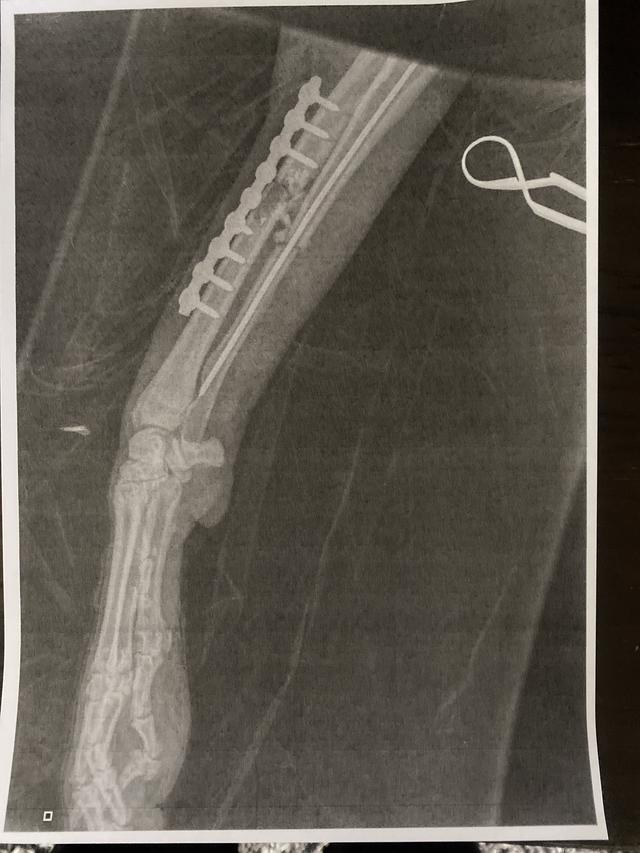

• X-ray post surgery

Post surgery

Delta is doing well but is still in quite alot of pain. She is going out for very short lead walks and while these were supposed to be getting a bit longer we have had to keep them short as she is struggling. She had her first physio session this week and we now have lots of stretches, exercises and massage to do to help her recover. She has a follow up xray on the 1st October which will tell us if the surgery was a success. She may need further surgery to remove the pins and plate once the leg is healed or worst case scenario lose her leg.